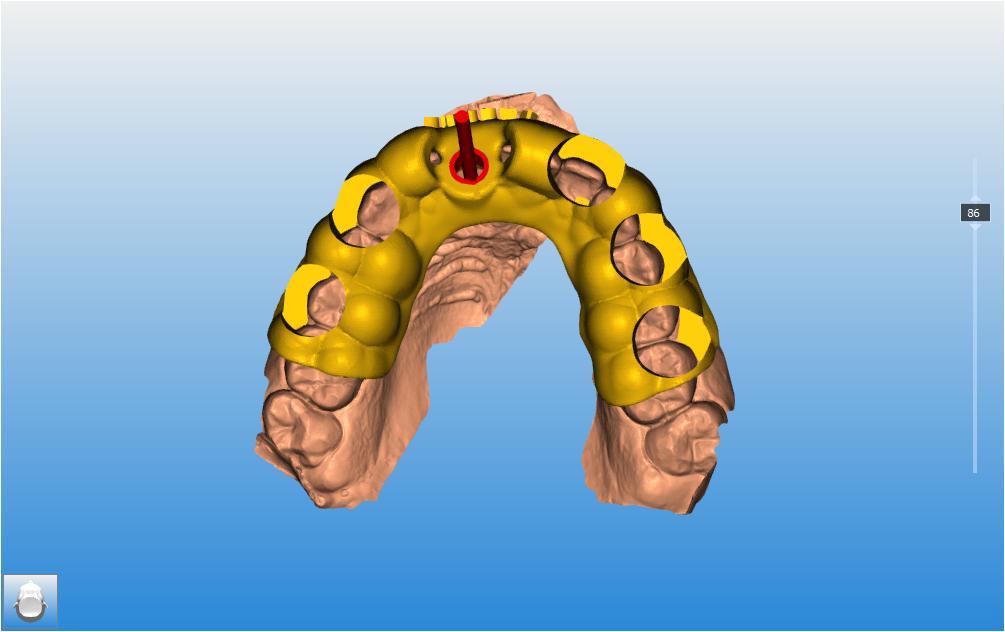

Le CBCT réalisé (fichiers dicom) est inséré dans le logiciel RealGuide pour permettre de l’associer avec

l’empreinte numérique de la patiente (Photo 8). Ces éléments nous permettent donc de simuler :

• L’avulsion de la dent 11

• L’évaluation des parois osseuses résiduelles

• La position implantaire idéale, en respectant l’axe prothétique et les contraintes anatomiques.

Un guide chirurgical a été réalisé pour guider la pose de l’implant selon la planification (Photo 9).